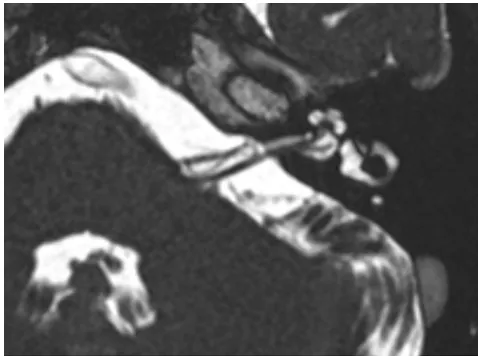

MRI(磁共振成像):显示患侧小脑前下动脉(AICA)血管袢压迫前庭耳蜗神经(负责听觉和平衡功能);

因患者无法长期耐受卡马西平,最终选择微血管减压术。手术采用乙状窦后入路,精准分离神经血管压迫点,植入特氟龙垫片解除压迫。